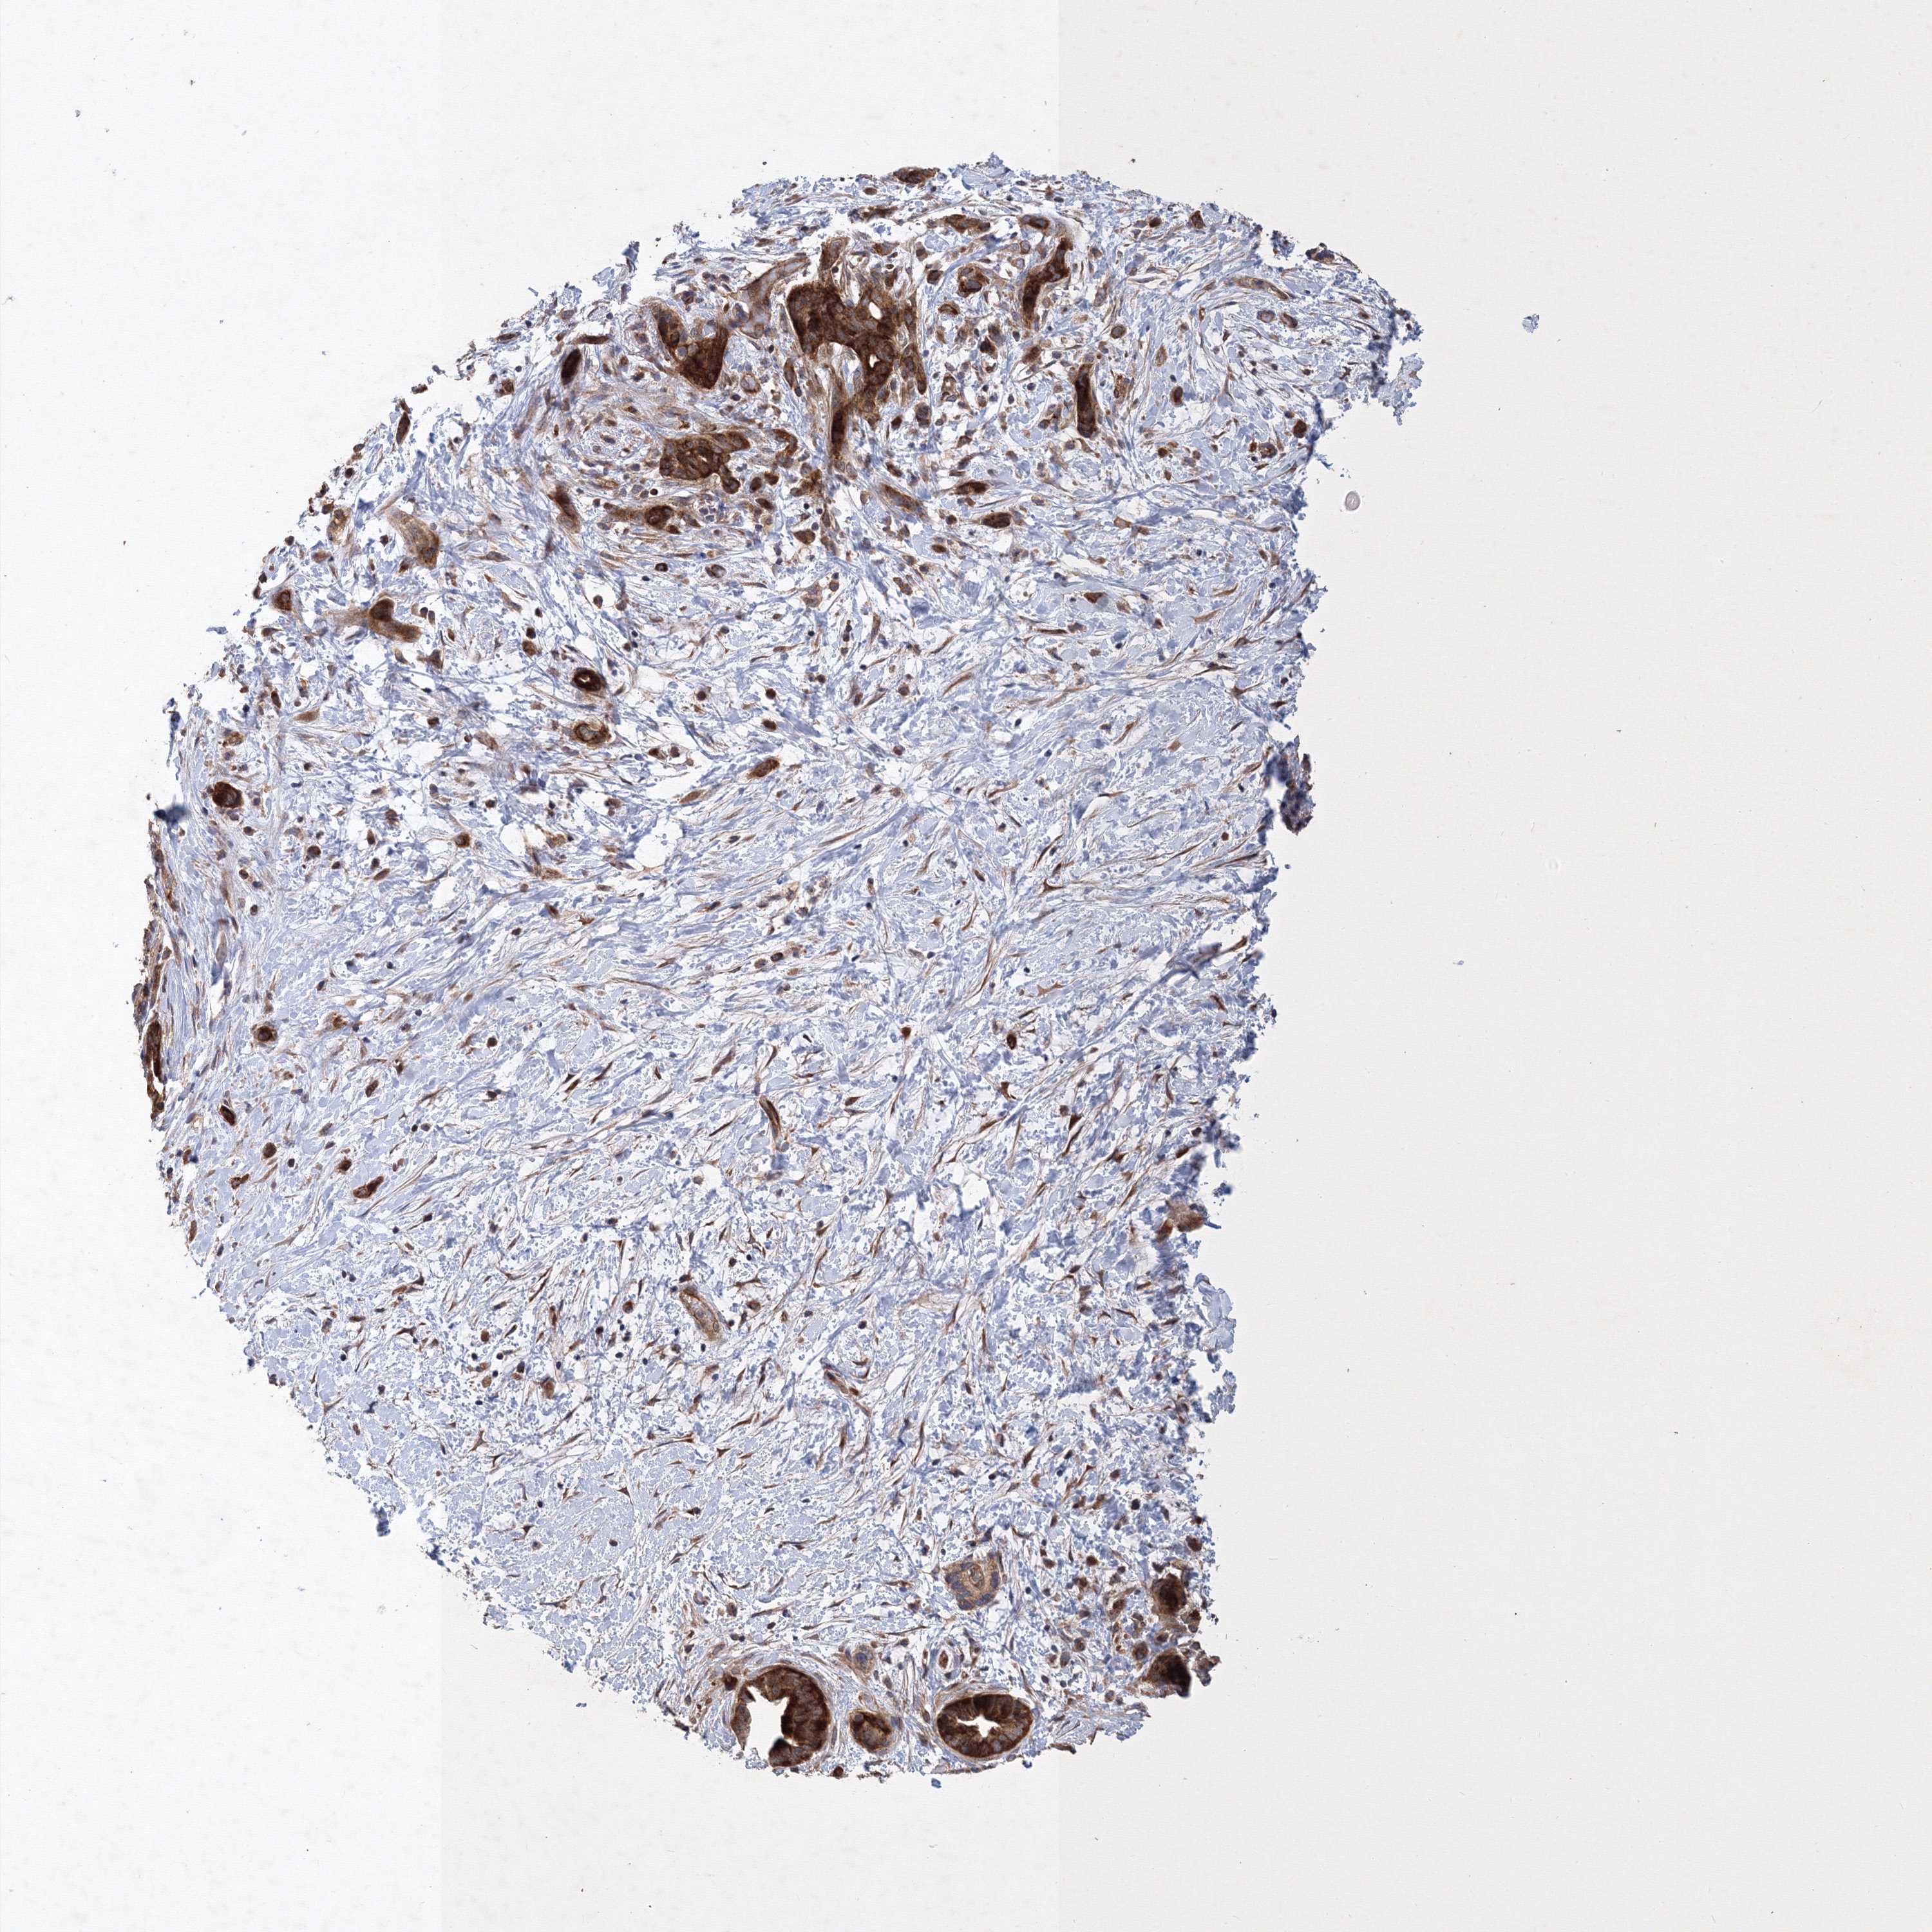

PANCREATIC CANCER - Protein expressioni

A mouse-over function shows sample information and annotation data. Click on an image to view it in a full screen mode. Samples can be filtered based on level of antibody staining by selecting one or several of the following categories: high, medium, low and not detected. The assay and annotation is described here.

Note that samples used for immunohistochemistry by the Human Protein Atlas do not correspond to samples in the TCGA dataset.

Antibody stainingi

Antibody staining in the annotated cell types in the current human tissue is reported as not detected, low, medium, or high, based on conventional immunohistochemistry profiling in selected tissues. This score is based on the combination of the staining intensity and fraction of stained cells.

Each image is clickable and will lead to virtual microscopy that enables deeper exploration of all samples and also displays staining intensity scores, fraction scores and subcellular localization as well as patient and tissue information for each sample.

Antibody HPA030943

Antibody HPA030944

Antibody HPA030945

Antibody CAB034184

Staining

High

Medium

Low

Not detected

Intensity

Strong

Moderate

Weak

Negative

Quantity

>75%

75%-25%

<25%

None

Location

Nuclear

Cytoplasmic/membranous

Cytoplasmic/membranous,nuclear

Adenocarcinoma, NOS